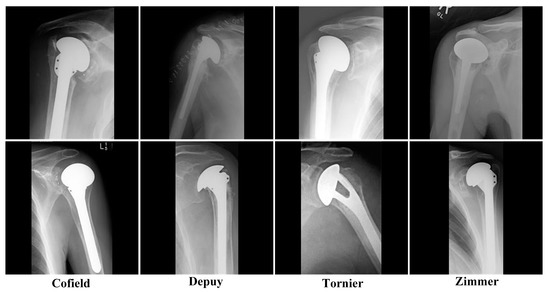

2.2. Dataset

| Training | Test | |

|---|---|---|

| Cofield | 75 | 8 |

| Depuy | 264 | 30 |

| Tornier | 64 | 7 |

| Zimmer | 134 | 15 |

| Total | 537 | 60 |